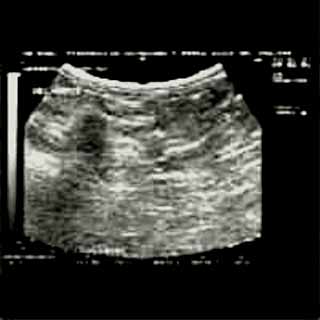

Για την καλλίτερη απόδοση της εξέτασης απαιτείται κεφαλή linear τουλάχιστον 7,5 ΜΗΖ. Ωστόσο και με κεφαλές 3,5 και 5 ΜΗΖ μπορεί κανείς να έχει καλά αποτελέσματα.

Οι απεικονίσεις των περιστατικών που επιδεικνύονται παρακάτω, έγιναν με κυρτές κεφαλές 3,5 και 5 ΜΗΖ, προκειμένου να φανεί, ότι και με τον εξοπλισμό αυτό, που σιγά-σιγά διαθέτουν όλο και περισσότερα ιατρεία, είμαστε σε θέση να έχουμε ικανοποιητικά αποτελέσματα.

Oι τελευταίες 4 απεικονίσεις έγιναν με ειδικό για μαστό ηχοβολέα linear, εναλλασσομένης συχνότητος 7,5-10ΜΗΖ.